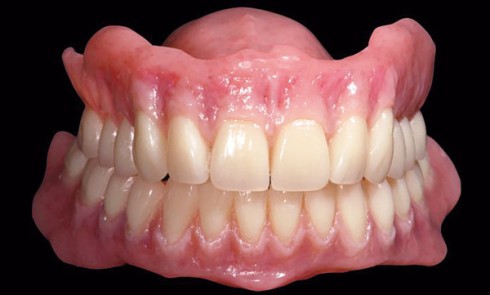

Aujourd’hui, grâce à la Conception et à la Fabrication Assistée par Ordinateur (C.F.A.O.), nous avons la possibilité d’améliorer la qualité...